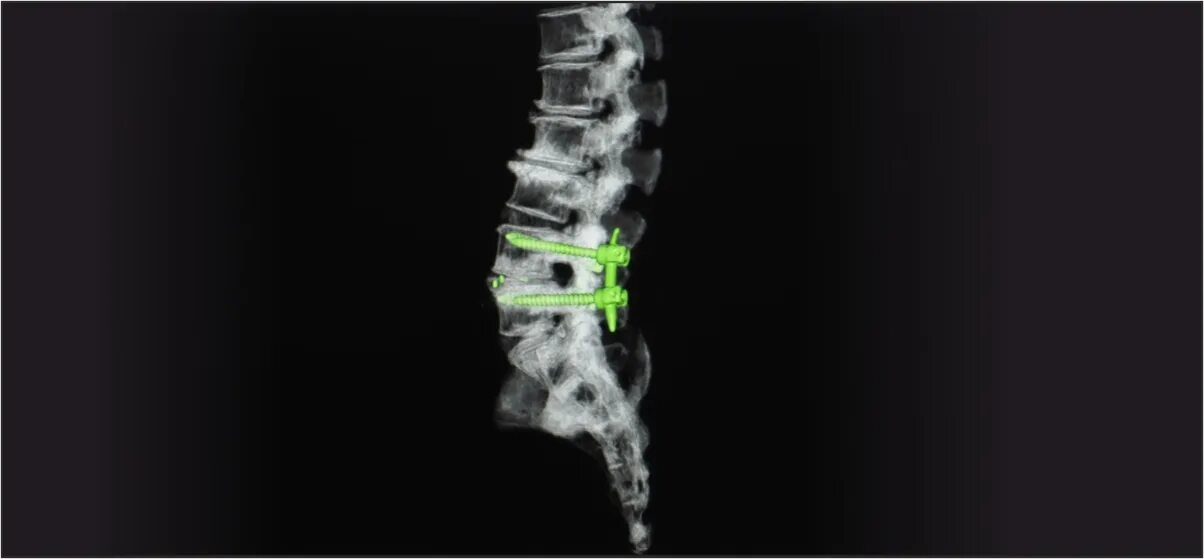

Установка кейджа в позвоночнике